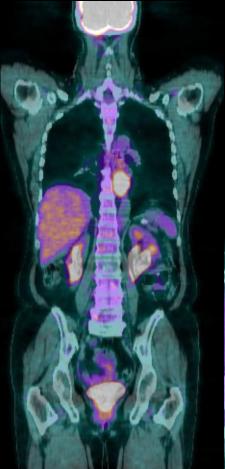

| - La medecine nucleaire PET scan en

association CT scanner ( PET/CT ) pour etude scintigraphique de la

clairence de oesophage , du RGO avec les subtance

radioactif de marque 99mTc et etude le bilan

d'extention gang;lionaire et metastatique des

neoformations . |

Image PET /CT en coupe

coronal ( frontale ): . Tumeur epidermoide 1/3 moyen

de oesophage avec metastase du foie , reins ,

ganglion pelvienne . et des os ... ( bilan

d'extention metastasique ) |